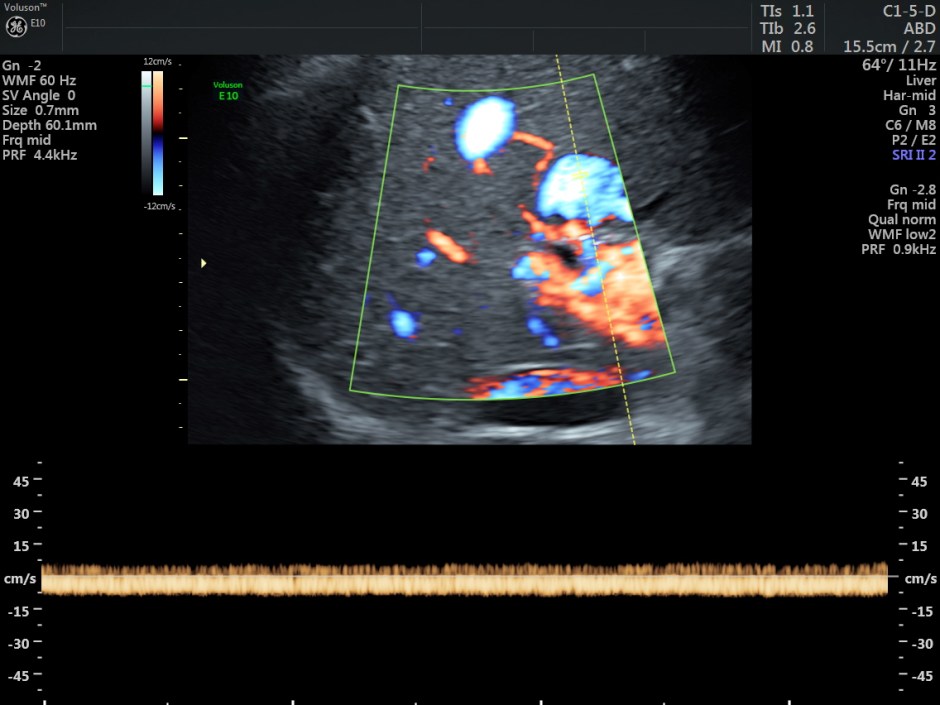

The venous flow is established by power doppler in the following pictures.

Reconstructed images show the feeding vessel and a vessel leaving the vascular structure.